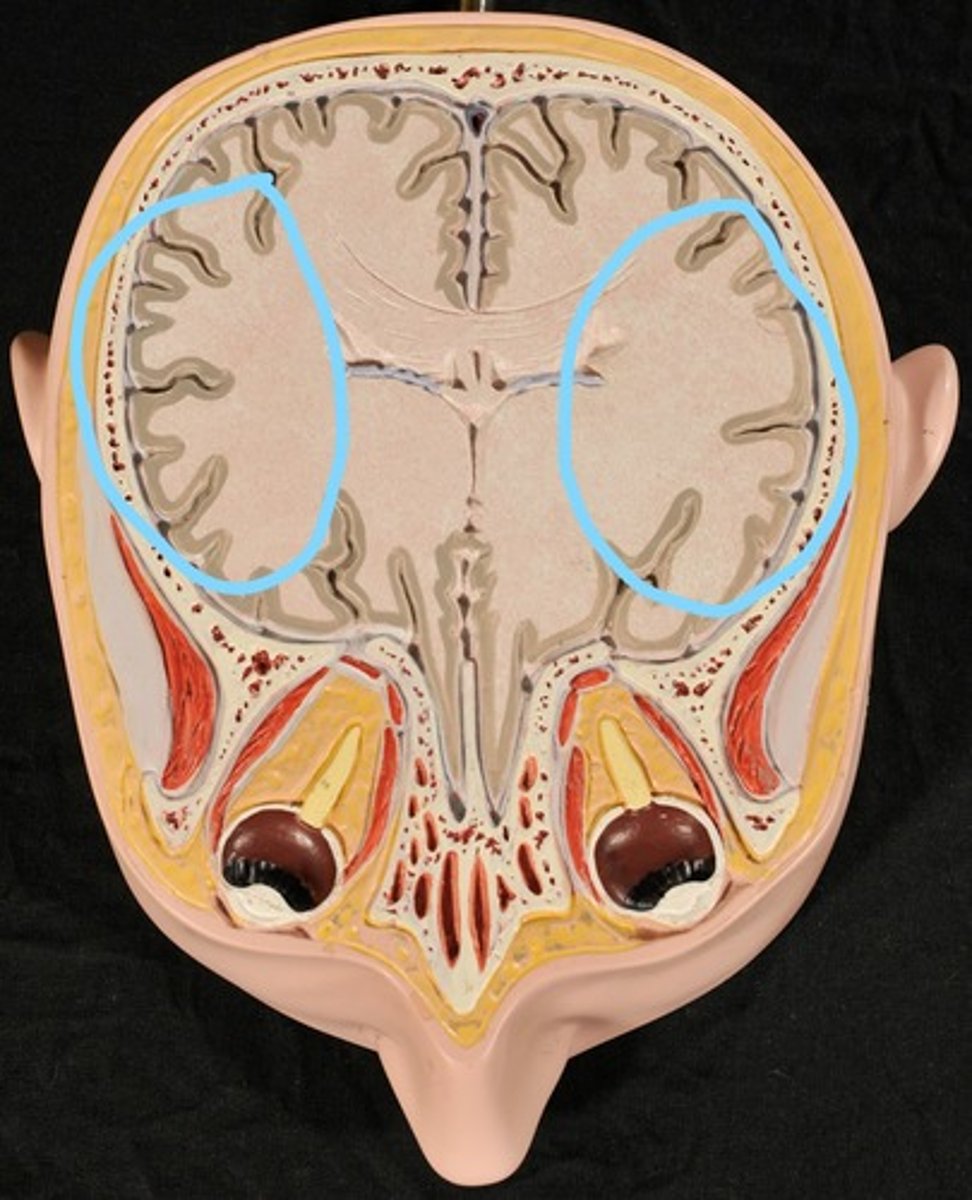

Identify the structures

Left Lateral Ventricle

Right Lateral Ventricle

Anterior horn of ventricle

Posterior horn of Ventricle

Inferior horn of ventricle

Cerebral Cortex (gray matter) (Slice 2)

Cerebral Medulla (white matter) (Slice 2)

Right & Left Parietal Lobes (Slice 2)

Right & Left Lateral Ventricles (Slice 2)